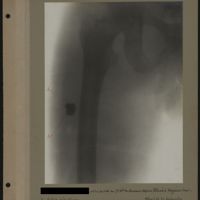

0005 - Page 1 - [Radiographie tête et cou]0005 - Page 1 - [Radiographie tête et cou]